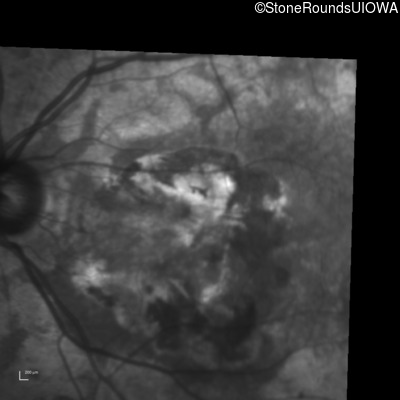

Infrared Fundus Photograph - Left - 20/160 -1

Exemplar